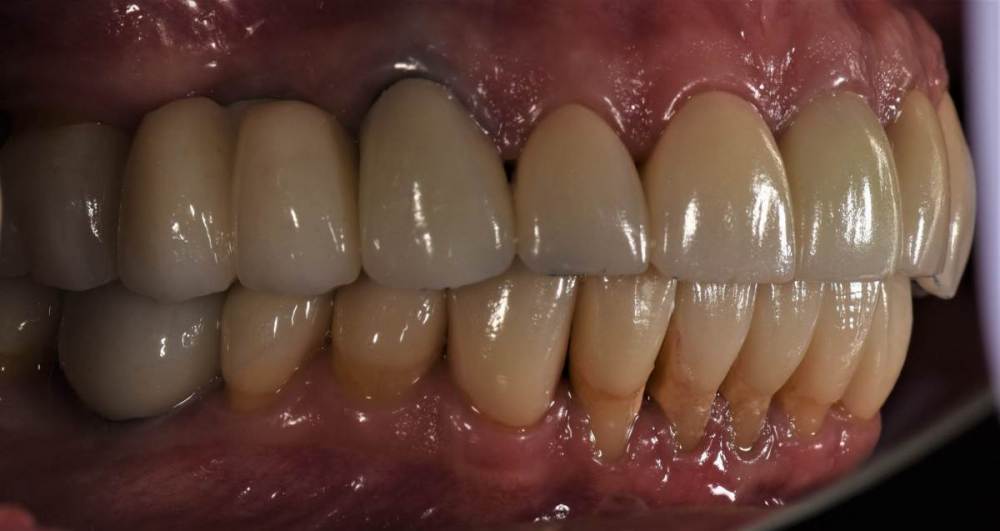

Финал работы:

DSC_3144.thumb.JPG.c9e60b8847f66dc01ba0e6e1113ab39b.JPGDSC_3145.thumb.JPG.1723748a079bc482f1a7e4534aff8f33.JPGDSC_3146.thumb.JPG.6dd4d0eb29dc3e6e92773c3c7892f692.JPGDSC_3147.thumb.JPG.e4f9cc2d841e3b7ff3aa73491ba9b4a3.JPGDSC_3148.thumb.JPG.0f174600adf2a49d65266a0ff665abfd.JPGDSC_3149.thumb.JPG.c9849be795d45b2573488d4545f3843f.JPGDSC_3150.thumb.JPG.6380366ecde7802fa32c6471b8b33883.JPGDSC_3153.thumb.JPG.1420d109d08ed1d6bd63447fe73eeed6.JPGDSC_3154.thumb.JPG.04b902149b3c0f9f2f1bcfa2e310c855.JPG

Фото спустя месяц после фиксации. Сначала нижняя челюсть, потом верхняя. Решение с передними нижними зубами - компромиссное. Все они витальные, имели 2-3 степень подвижности. После исправления положения нижней челюсти и установления правильных окклюзионных контактов - 1-2 степень подвижности. По поводу гигиены пытаемся.